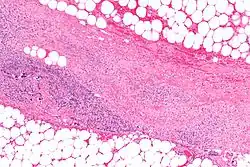

Necrotizing enzymes destroy cells and tissue. One of the best known examples is an exoenzyme produced by Streptococcus pyogenes that causes necrotizing fasciitis in humans.

Many exoenzymes are also used as virulence factors. Pathogens, both bacterial and fungal, can use exoenzymes as a primary mechanism with which to cause disease. The metabolic activity of the exoenzymes allows the bacterium to invade host organisms by breaking down the host cells' defensive outer layers or by necrotizing body tissues of larger organisms.[3] Many gram-negative bacteria have injectisomes, or flagella-like projections, to directly deliver the virulent exoenzyme into the host cell using a type three secretion system.[10] With either process, pathogens can attack the host cell's structure and function, as well as its nucleic DNA.[11]